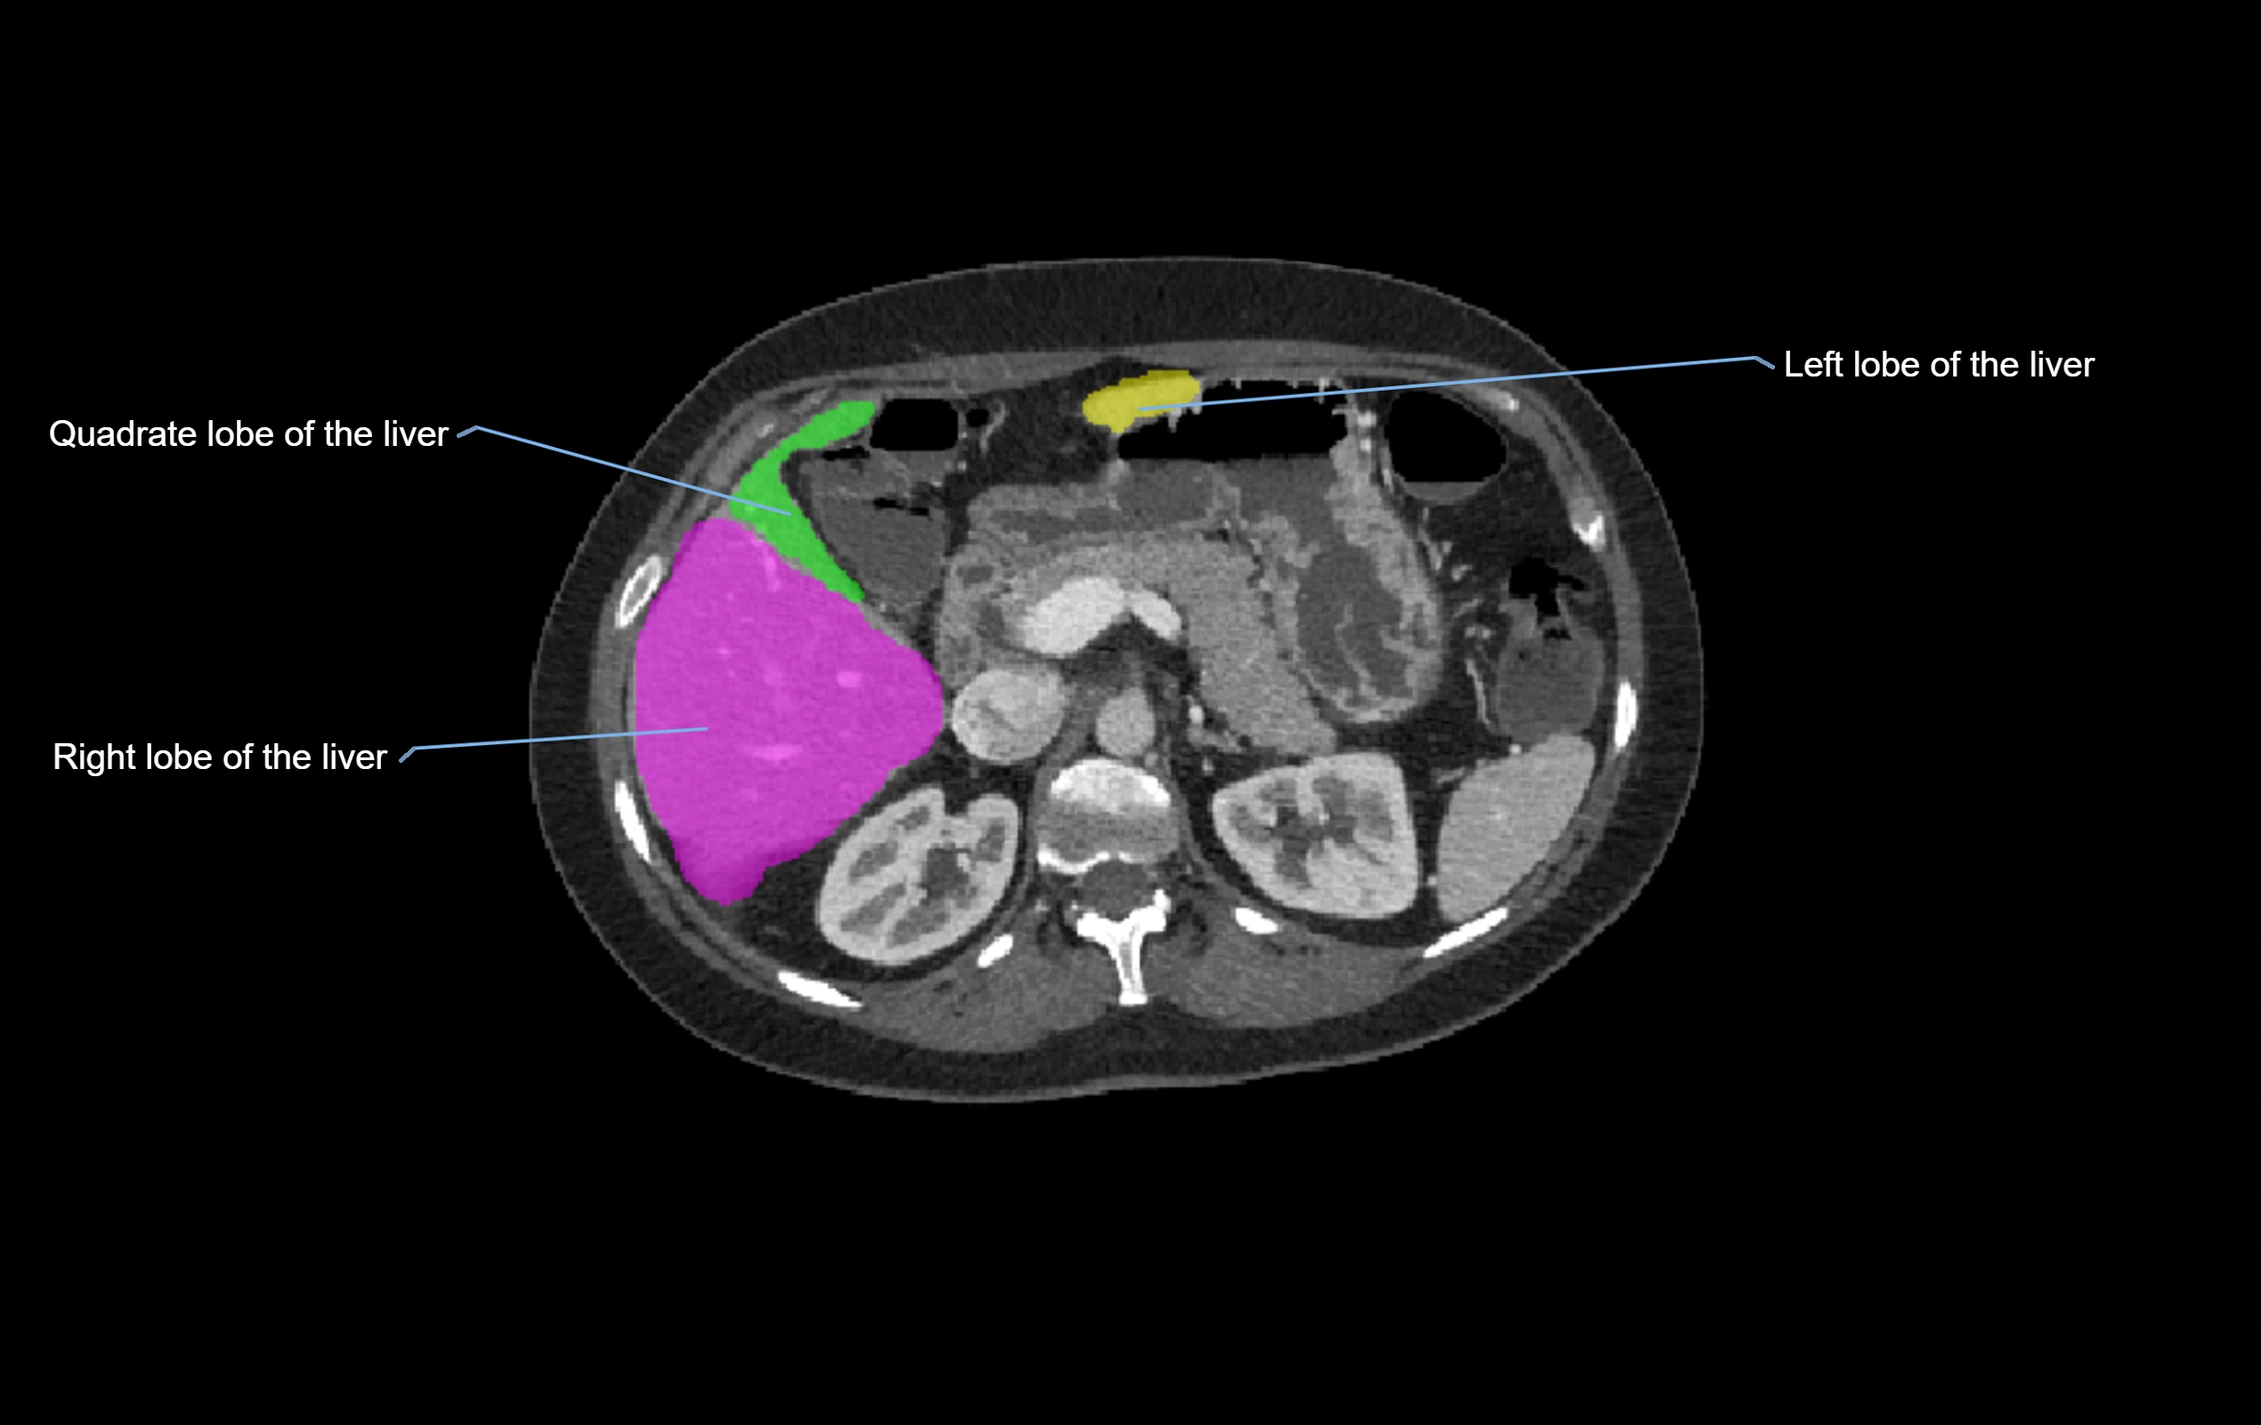

The caudate lobe of the liver is a distinct anatomical subdivision of the liver, designated as segment I in Couinaud’s classification. It lies on the posterior surface of the liver, between the fissure for the ligamentum venosum (left boundary) and the groove for the inferior vena cava (IVC) (right boundary). Superiorly, it is related to the posterior liver surface, and inferiorly it is separated from the left lobe by the porta hepatis.

CT Image

image